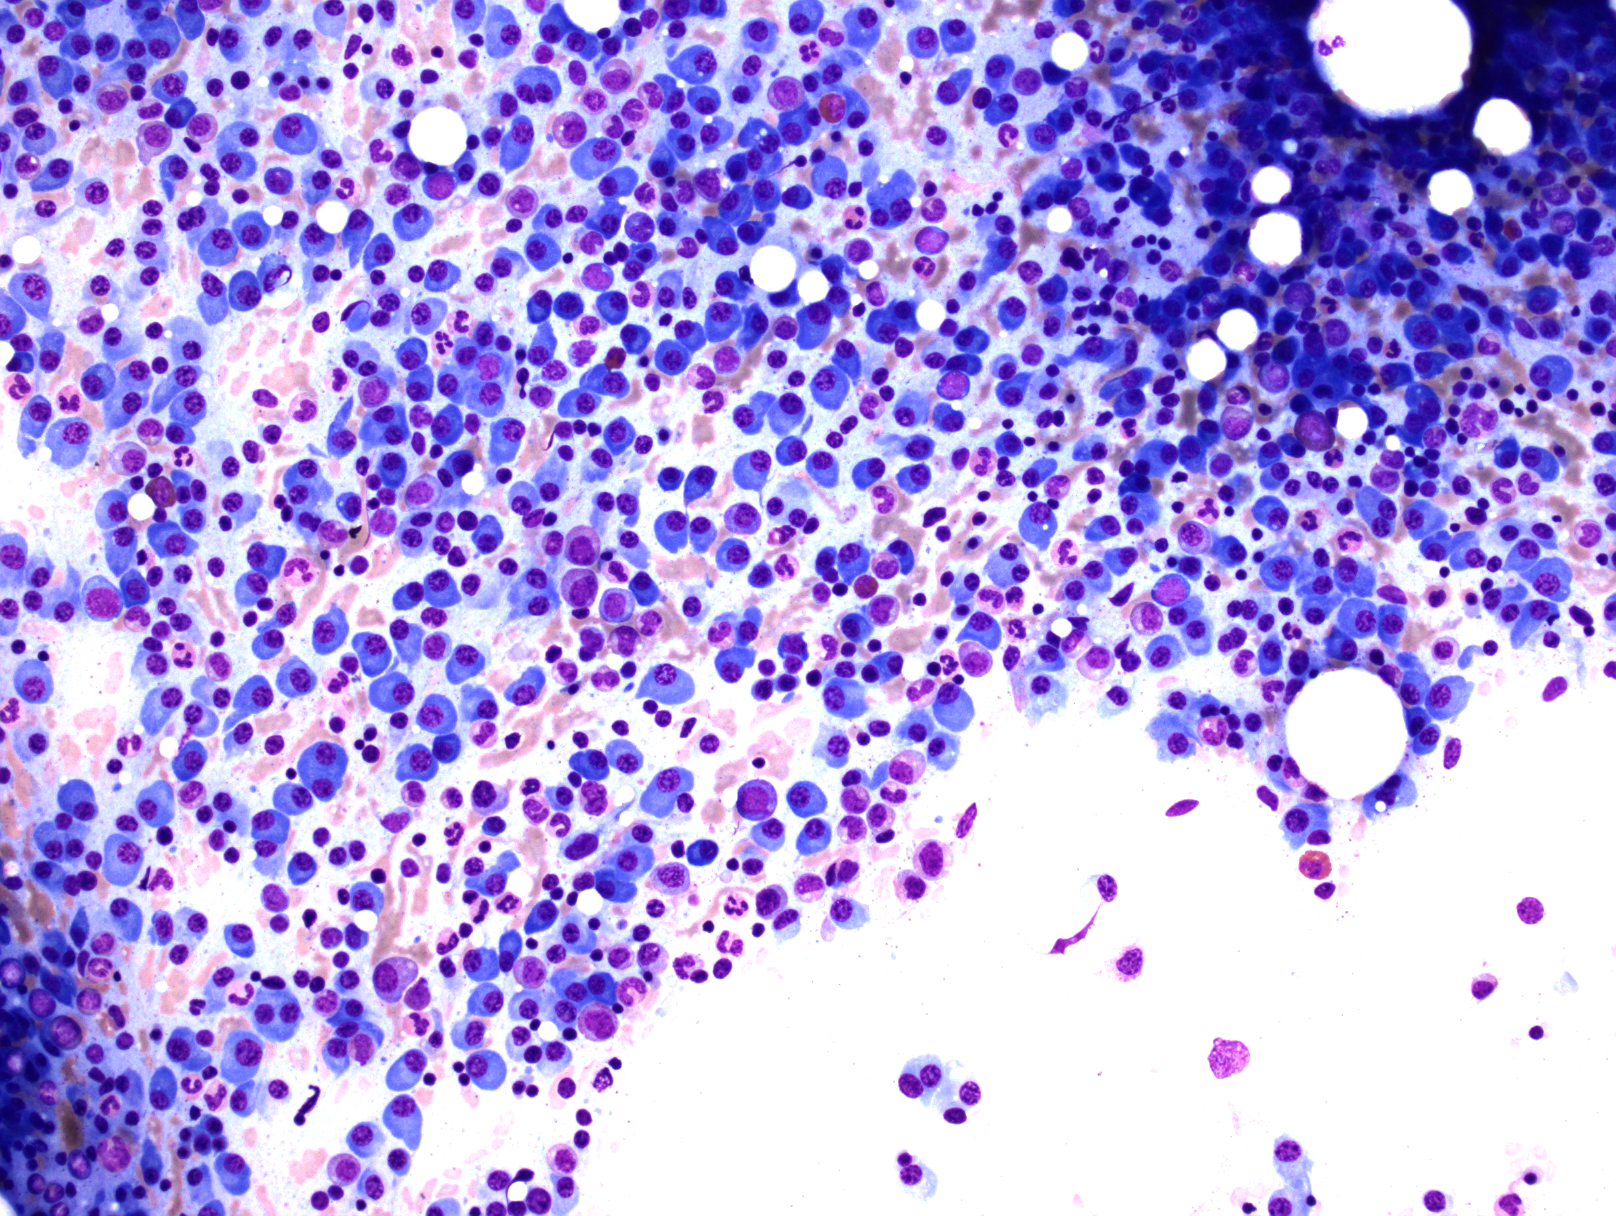

根据疾病的不同阶段,骨髓浆细胞浸润方式可以表现为间质性、局灶性或弥漫性浸润。一般浆细胞数达骨髓容量 30%,浆细胞骨髓瘤可能性很大。

肿瘤浆细胞形态变化很大,可以是成熟性、中间性、不成熟性、浆母细胞性或多形性。小细胞型则类似淋巴浆细胞,容易误诊为 LPL 或套细胞淋巴瘤。

浆细胞白血病(Plasma Cell Leukemia, PCL ) :外周血中肿瘤性浆细胞数>20%白细胞总数,或浆细胞绝对计数>2.0×109/L。多数 PCL 病例(60-70%)为原发(占所有 PCM 病例的 2-4%),中位发病年龄较轻。少数由 PCM 进展而来(占所有 PCM 病例 1%)。骨髓通常广泛或弥漫浸润,也累及其它脏器。免疫表型上与 PCM 同,但多数病例 CD56 阴性。临床表现为侵袭性,预后不良,生存期短。